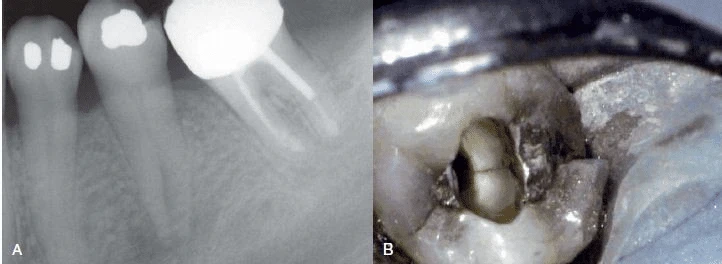

Hình 4. Thường khó chẩn đoán nứt dọc chân răng trừ khi là phải tháo bỏ miếng trám cũ

Đánh giá miếng trám/phục hình trên răng

Răng mang miếng trám nhỏ hoặc không mang miếng trám, không có sâu răng nhưng tuỷ răng chết thì khả năng nghi ngờ cao rằng bị nứt dọc chân răng. Ngoại trừ những trường hợp chấn thương khớp cắn, bệnh lý hệ thống (như nhiễm Herpes Zoster trong miệng), hoặc phẫu thuật vô tình làm chết tuỷ răng (như phẫu thuật xoang, phẫu thuật chỉnh hình, nhổ răng và cấy chuyển răng), nứt dọc chân răng cũng là một trong những lý do khiến răng chết tuỷ.

Một răng có bệnh lý nội nha tái phát, răng này trước đây đã được đóng chốt và là răng trụ của một cầu răng vói thì cũng có thể nghi ngờ do nứt dọc chân răng. Lực xoắn trong quá trình ăn nhai tác động lên cầu vói và lực nhún có thể tạo áp lực lên chân răng dẫn đến nứt dọc. Các triệu chứng diễn ra dai dẳng ở một răng mang miếng trám trong thân răng cũng gợi ý trường hợp nứt dọc chân răng.

Nhìn chung thông thường sẽ có lý do khiến răng chết tuỷ hoặc đau. Bác sĩ cần đánh giá điều trị phục hồi răng đang có, tìm lý do răng chết tuỷ hoặc các triệu chứng khác, và trong các chẩn đoán phân biệt cần bao gồm cả trường hợp nứt dọc chân răng.

Hình 5. Răng không mang miếng trám hoặc mang miếng trám nhỏ, răng không sâu răng hoặc sâu nhỏ nhưng tuỷ răng bị hoại tử.

Hình 6. Răng đã điều trị nội nha là một phần của phục hình cầu răng vói